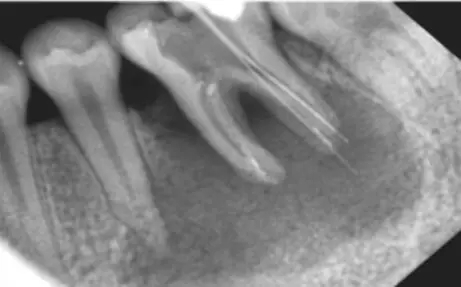

看下圖X光片是不是覺得欠充了呢?

其實:X光片確定長度經(jīng)常性引起超充?

X線片法缺陷

1) 三維結(jié)構(gòu)投射在二維平面上,因投射角度不一樣,數(shù)據(jù)容易出錯。

2)根尖孔不能體現(xiàn)在牙片上,而80%以上的根尖孔都不在牙齒根尖而是在側(cè)邊。

根尖開口在側(cè)邊時,X線片投射引起長度偏差錯誤。

根尖開口距離牙齒根尖距離越大,誤差越大,會引起嚴重超充。